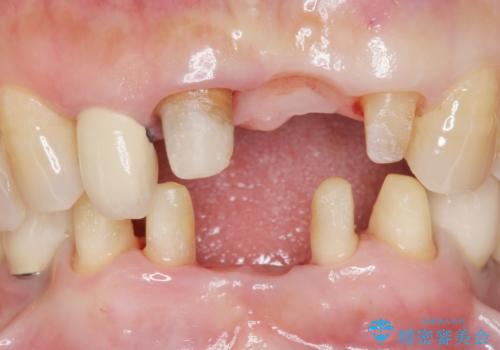

- 上下の前歯が抜けそうだとのことで来院されました。

精査したところ、動揺の著しい上下の前歯は重度の歯周病により保存不可能と判断しました。

ブリッジ、インプラント、義歯の選択肢の中で上下前歯ともにブリッジをご希望されました。

抜歯後歯肉の治癒を十分に待ったのち、ブリッジによる補綴治療を行いました。